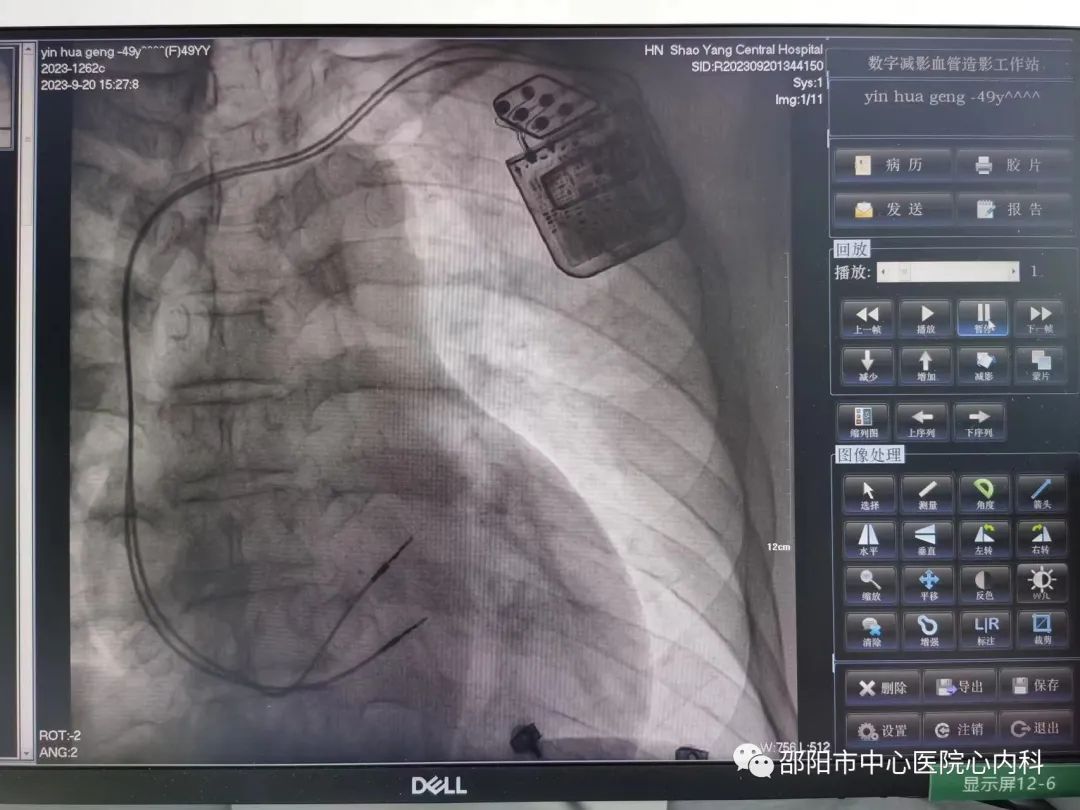

我院收治患者后,立即详细了解患者病情,经充分评估后故建议病人植入CCM。在院领导、各职能部门及科室同仁的支持下,手术顺利完成!

CCM植入手术是将刺激电极植入到患者心室,在心脏搏动的绝对不应期里释放电刺激,能够明显改善心衰患者心脏功能和临床症状,提高患者生活质量。